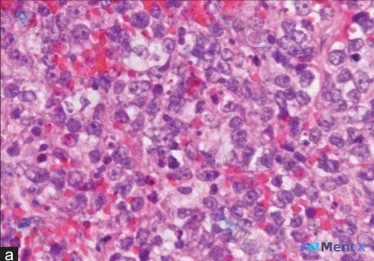

今天看到一张很有警示意义的HE染色病理片,整理一下完整的分析思路,和大家一起讨论。 先看镜下核心表现 - 染色与结构:标准HE染色,核呈深蓝色/紫黑色,胞浆粉红色;完全看不到正常的腺管、小叶或鳞状上皮结构,细胞呈实性、弥漫性片状铺展,边界不清,黏附性低。 - 细胞异型性:核普遍增大、大小不等、多形性...